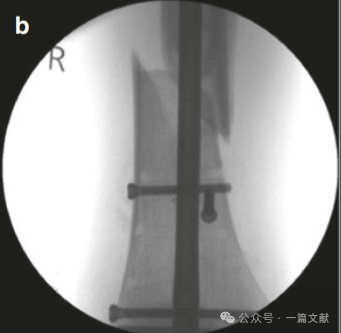

随后的阻挡螺钉被置入在髓内钉的另一侧,即拇指和手指放置在骨头上的相反侧(按压的对侧)。如下图:本例展示了仅在远端骨块(干骺端)打入两枚阻挡钉,首先在靠近骨折线的近端打入一枚阻挡钉,不足以完全纠正畸形,随后在远端骨块髓内钉对侧的远端打入第二枚阻挡钉。